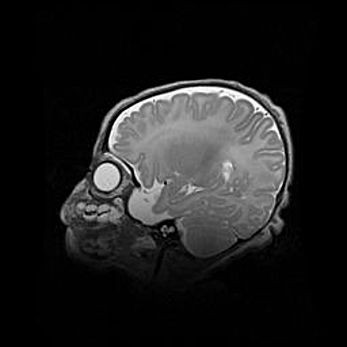

Церебральная ишемия II.

Возраст: 5 дней

Вес: 3400 г

Пол: женский

Окружность головы: 35 см

Срок гестации: 39 недель

Церебральная ишемия – это заболевание, характеризующееся недостаточностью (гипоксией) либо полным прекращением (аноксией) снабжения мозга кислородом по причине закупорки одного или нескольких сосудов. Это приводит к  что метаболическим расстройствам различной степени тяжести в тканях головного мозга, развитию коагуляционных некрозов и гибели нейронов.